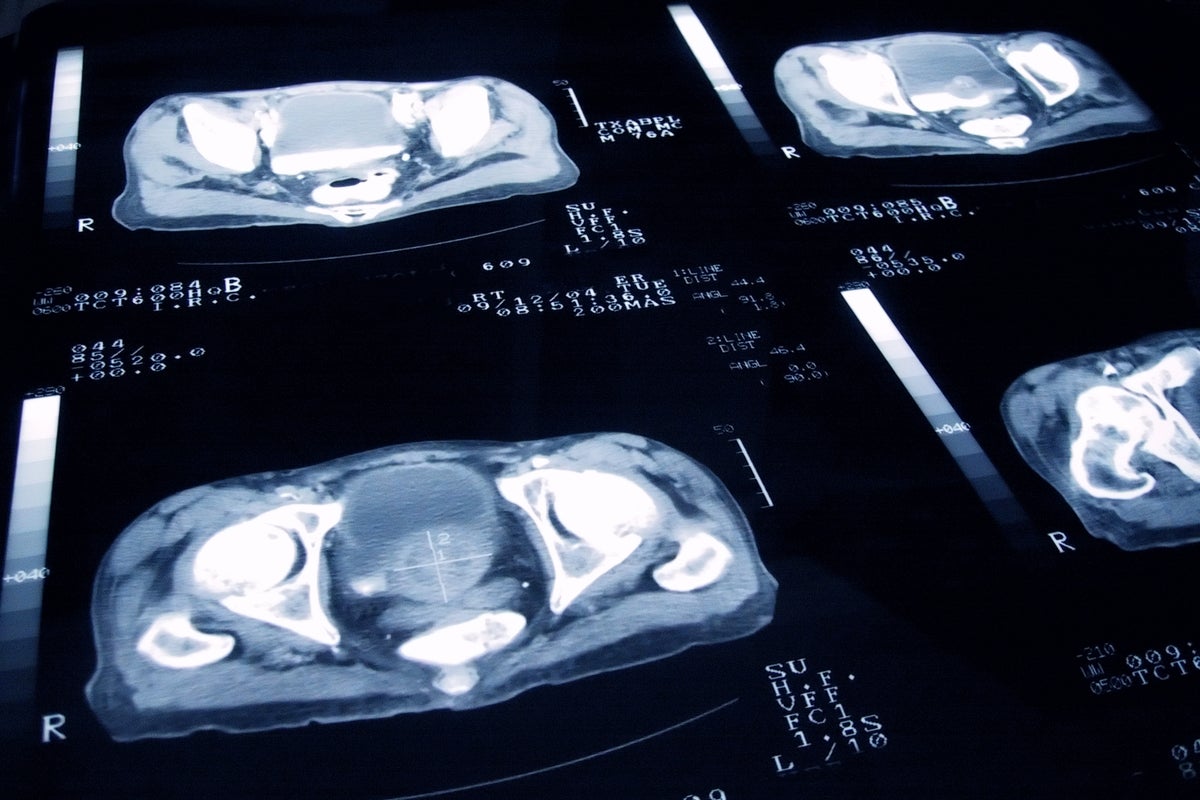

open image in galleryThe current position of the committee is that the prostate specific antigen (PSA) blood test, which is usually the first step towards a diagnosis, is not accurate enough as a primary screening testMen aged 50 or over can also ask their doctor for a PSA test even if they do not have symptoms.

open image in galleryThe UK National Screening Committee will make recommendations to the Government on Friday on whether it believes more men should be screened for prostate cancer (PA)A major new prostate cancer screening trial, backed by £42 million of funding from Prostate Cancer UK and the Government, is looking at whether using MRI or other scans, combined with PSA, could tip the balance in favour of a nationwide screening programme.